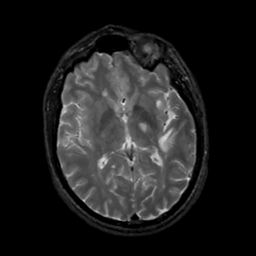

MR Study #5, March 10, 1991 -- Slice #27

[Home][Help][Clinical][Tour 1][Tour 2] Slice 27